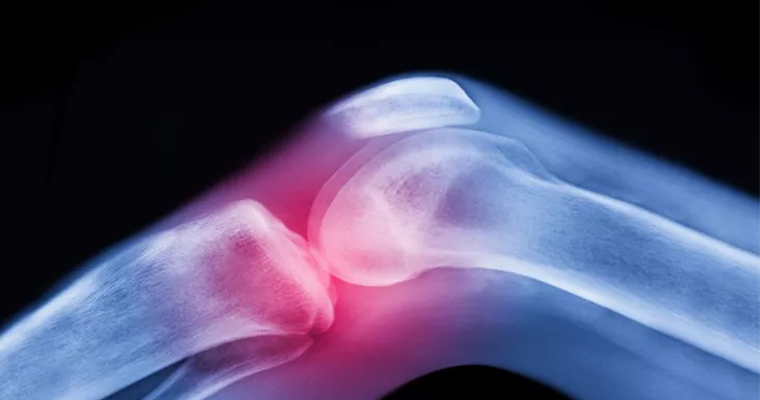

Joint replacement aims to restore painless motion to a joint and function to the muscles, ligaments, and other soft tissues that control the joint. Either a part or the total damaged bone is removed and replaced with artificial components made out of metal and polyethylene and the bones of the joint are "realigned" so that the weight that passes through the joint is normally distributed. Hip and knee the major weight bearing joints are the most commonly affected joints and are commonly replaced. Ankles, shoulders, elbows, wrists and fingers can also be replaced.

Joint replacement relieves pain, restores function and the newer type of joints allows unrestricted activities.